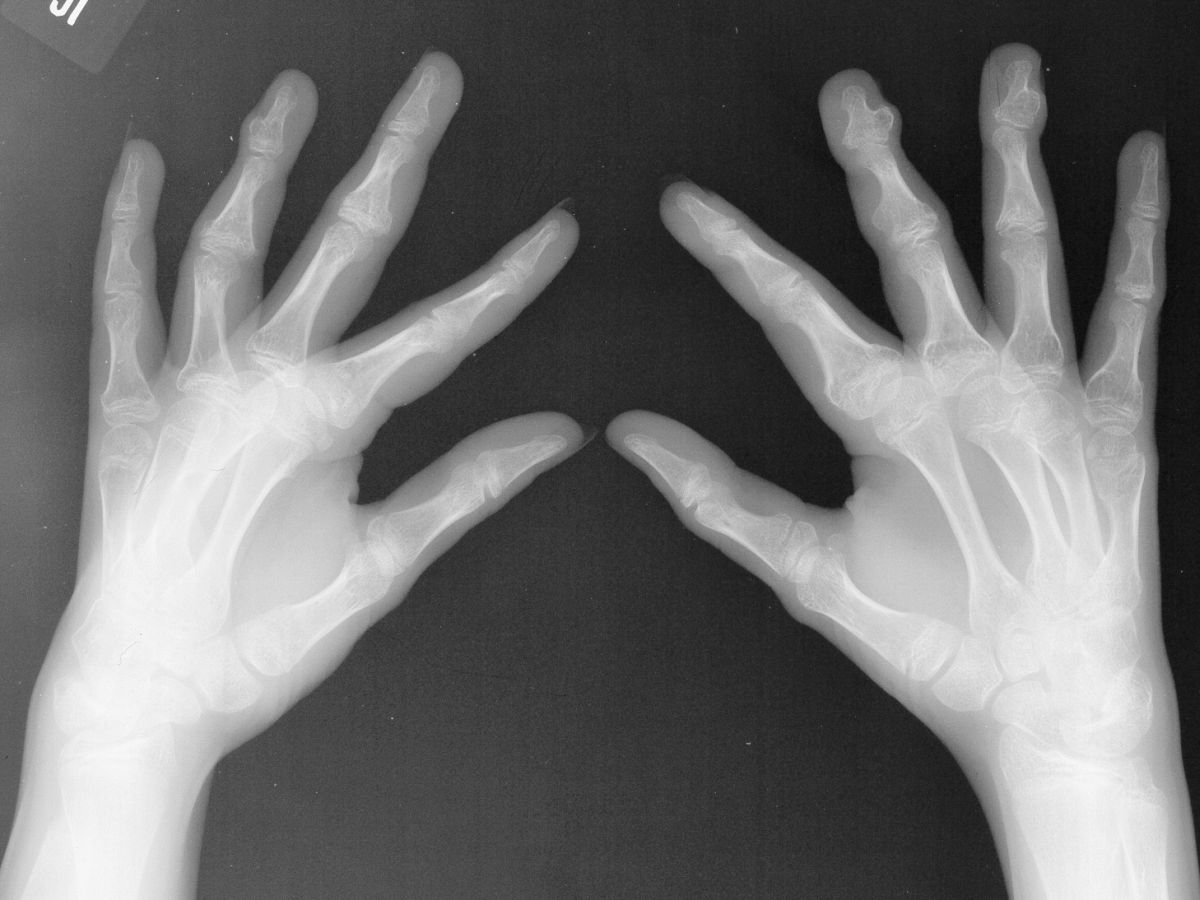

Nail deformities may result from growths changing the contour of the germinal matrix. These may appear permanent, but normal nail plate contour can be restored if the mass effect is corrected without damaging the germinal matrix. These five cases demonstrate the recovery potential of the nail bed in this circumstance.

Nail deformity from subungual bone tumor. This patient has multiple hereditary exostoses.